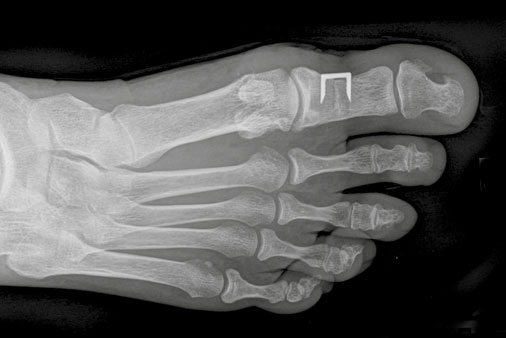

Bei stärkerer Fehlstellung oder wenn zusätzlich auch eine Verkrümmung innerhalb der Großzehe (Hallux valgus interphalangeus) vorliegt, kann eine Akin-Operation durchgeführt werden.

Hallux valgus nach Akin-Operation im Röntgenbild